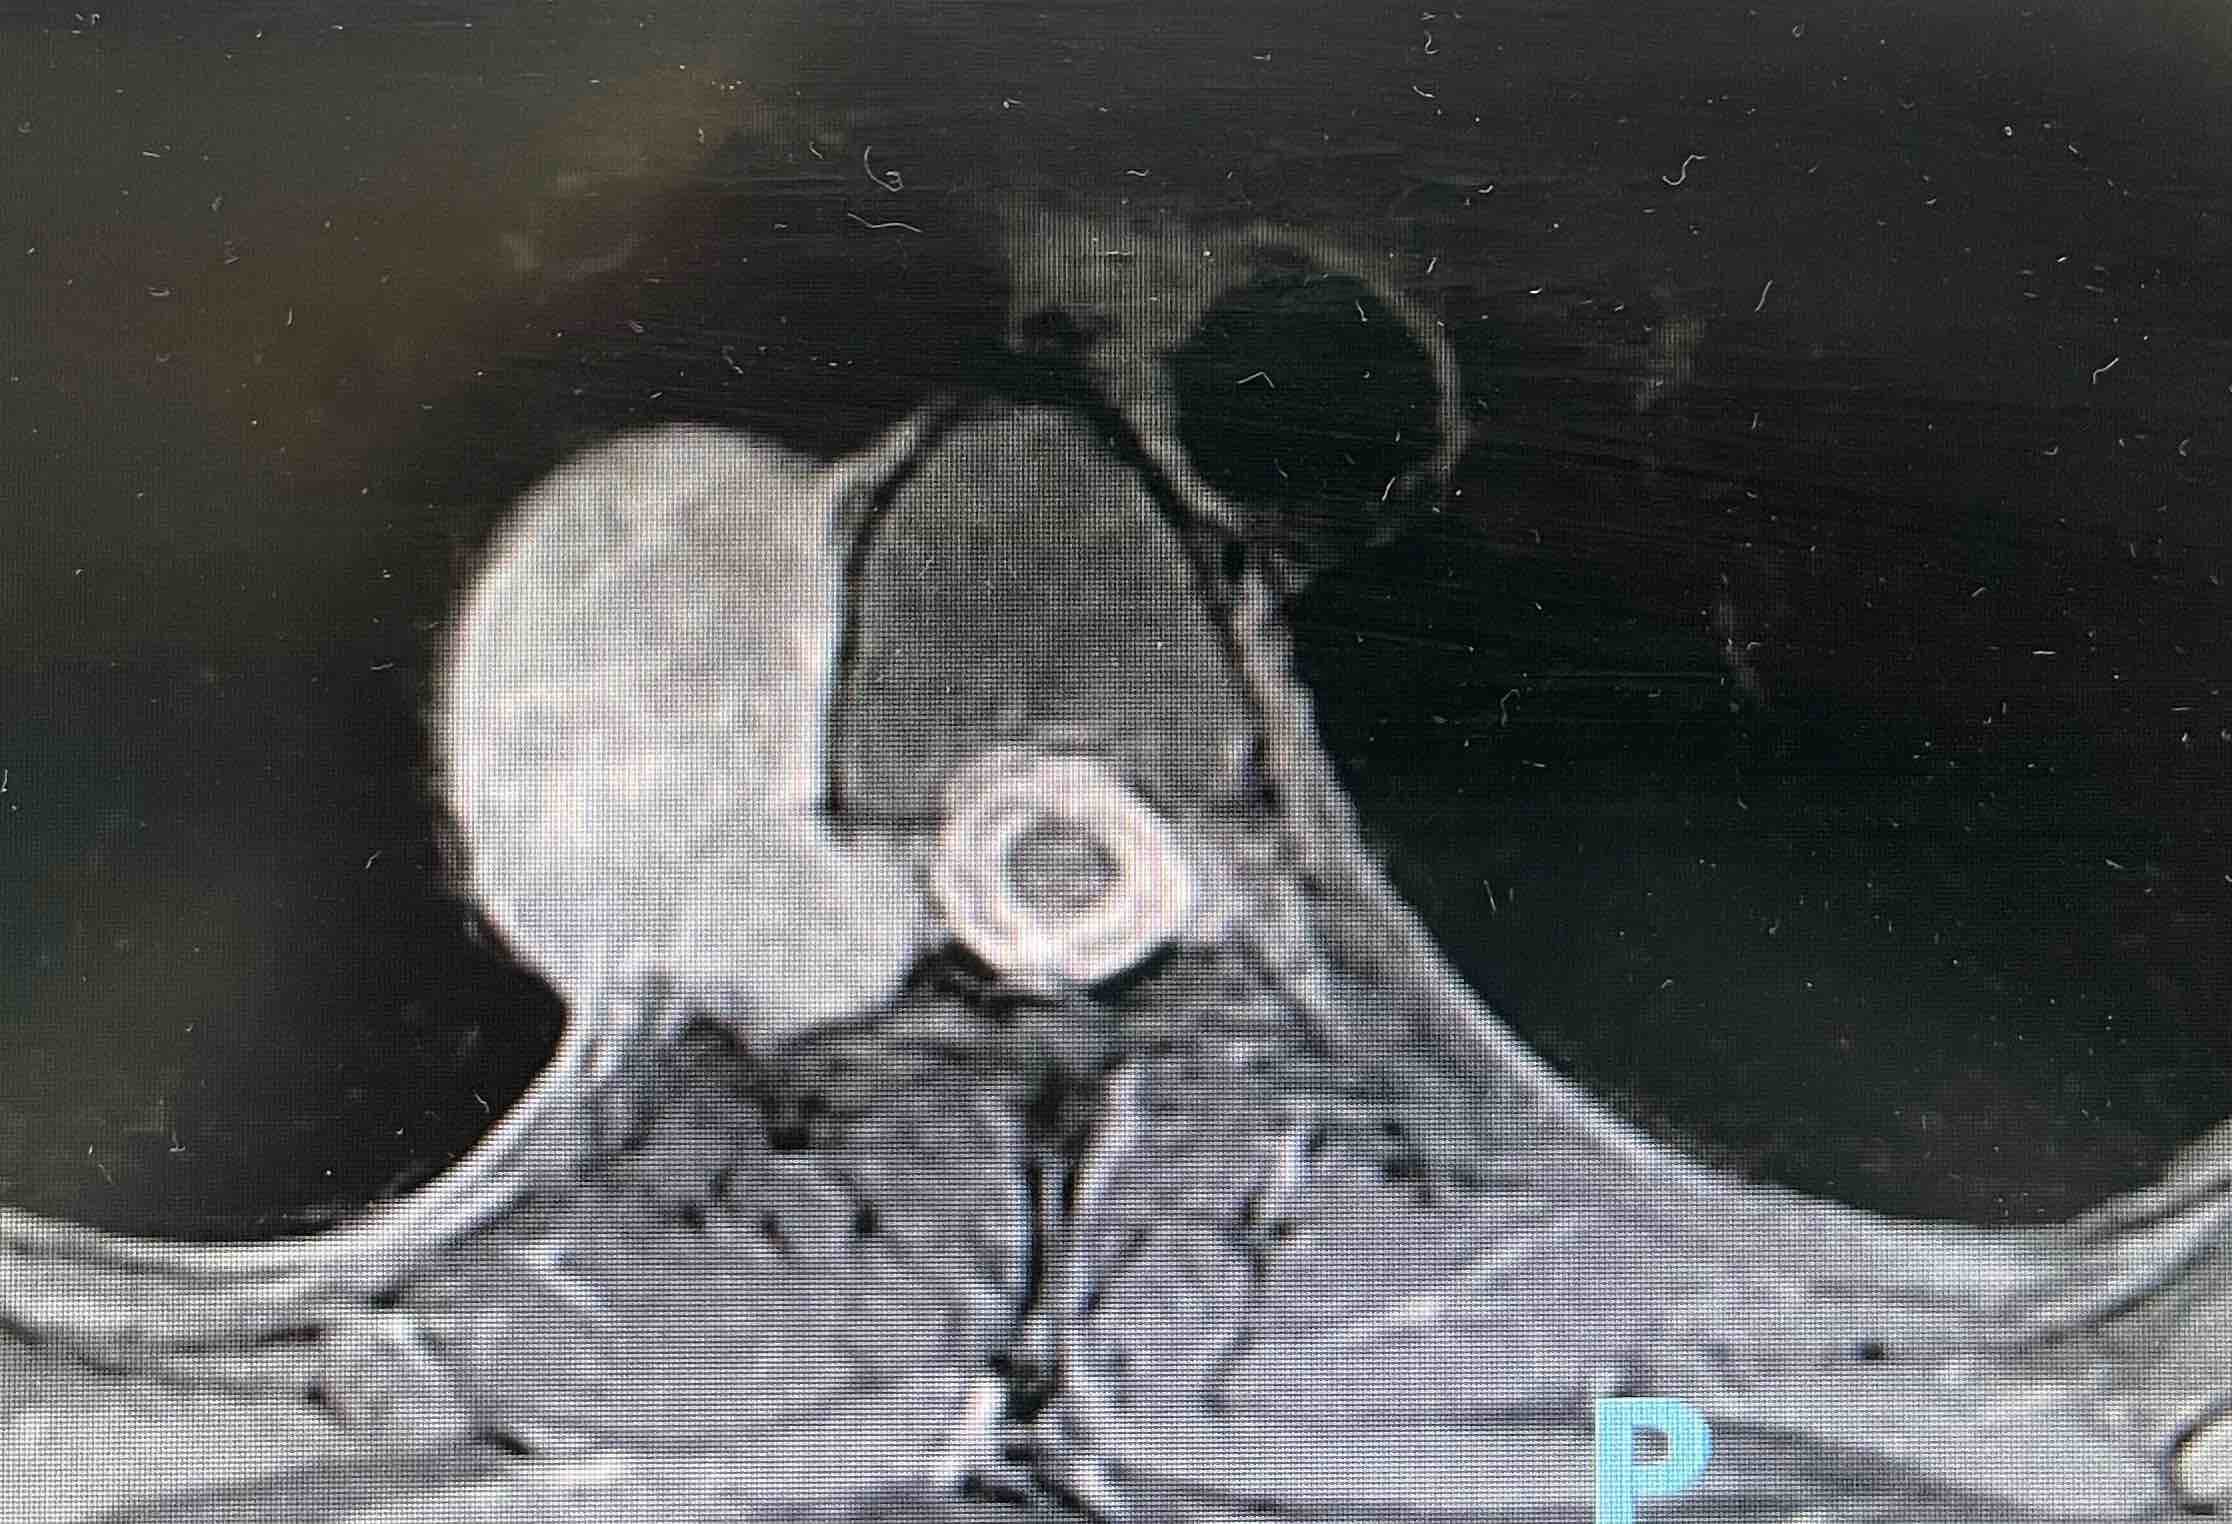

神经鞘瘤是起源于神经鞘雪旺细胞的一种良性肿瘤,常与神经根相连,可发生囊性变、坏死与出血,在椎管或椎体呈哑铃状。亦可发生于交感神经、迷走神经和喉返神经,肿物多有完整包膜,多为不规则分叶状和卵圆形,少数呈球形,表面光滑,目前病因尚不完全明了。

发病年龄20-40岁,根性疼痛为最早症状,临床典型症状为坚实结节、酸麻感、感觉及运动障碍。椎管内或累及压迫脊髓可出现不全瘫症状。神经鞘瘤生长缓慢,病程长。本病非手术治疗难以治愈,手术治疗方法是主要的治疗手段。

神经鞘瘤是否手术由肿瘤的生长部位、症状严重程度等决定。若肿瘤较小,无任何症状,可采用一般治疗,定期复查复诊即可;若肿瘤较大,或引起了疼痛、神经根性等症状,需采用手术治疗。部分无法切除或切除不彻底的病例需要多学科、放射治疗等。